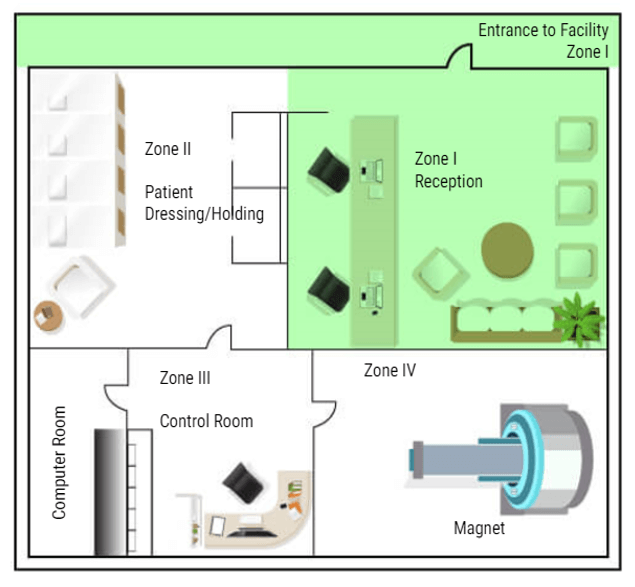

- List the four zones of MRI and give an example for each zone

Now that we know what types of things to be concerned about in and around the MRI suite, we will now discuss MRI Zones and who can be in each zone.

Why Zones Are Important

In MRI we divide the work area into four zones. Each zone is very specific about who may enter and under what conditions. All zones must be marked in and around the MRI suite. There must also be a clear definition of where one zone ends and one begins, such as a doorway, chain/rope or another clearly visible sign. The signage should include who is allowed beyond that point. Let’s look at each zone:

Zone 1

Zone 1 is for the general public. Anyone can be in zone one. Some examples are hallways near the MRI area, the main waiting room, or a shared waiting area with other departments. There is NO screening needed to be in Zone One. While in zone one the patient may be asked to complete a screening sheet or be asked some basic safety questions before being moved to zone II.

Zone 2

Zone II is where a more thorough screening will take place. The patients will also be prepped for their scans in this area – changing clothes, removing all metal items and placing them in a safe place. Patients are only permitted to enter zone II when accompanied by a healthcare employee. Family members may also be permitted in Zone II accompanied by the healthcare worker without being screened. But this is the anyone not screened or cleared my go in the MRI area. ALL questions should be answered while the patient is in this area. Even if the patient has completed a screening form, they are not permitted beyond this point until they are cleared or accompanied by Trained MRI professionals.

Zone 3

The next zone is Zone three. This is the control area, where the MRI technologist would operate the scanner. Patients should be accompanied by an MRI safety trained individual to enter zone three. People who have not removed loose metals, or who have pacemakers or other unsafe medical devices, should not be permitted in zone III because of the proximity to zone IV. A screened but uncleared person may enter zone III ONLY under strict supervision by trained personnel, such as a patient who just wants to look at the MRI scanner to decide if they will be able to tolerate the exam.

Zone 4

The final zone is zone IV, the MRI scan room. ONLY CLEARED patients are permitted to enter Zone IV, accompanied by trained MRI personnel. The final step of clearance, while in zone III, should be to check the patient one last time for loose metals, other electronic devices and a last check of the critical screening questions. ACR suggests asking these questions a minimum of three times. Once At scheduling, once at screening and once at clearance. As an additional safety measure, many facilities build a metal detector into the doorway between Zone 3 and Zone 4. But there are hand-held devices that work well too and they are less expensive. Once the patient is cleared they can be taken into the MRI room and scanned.